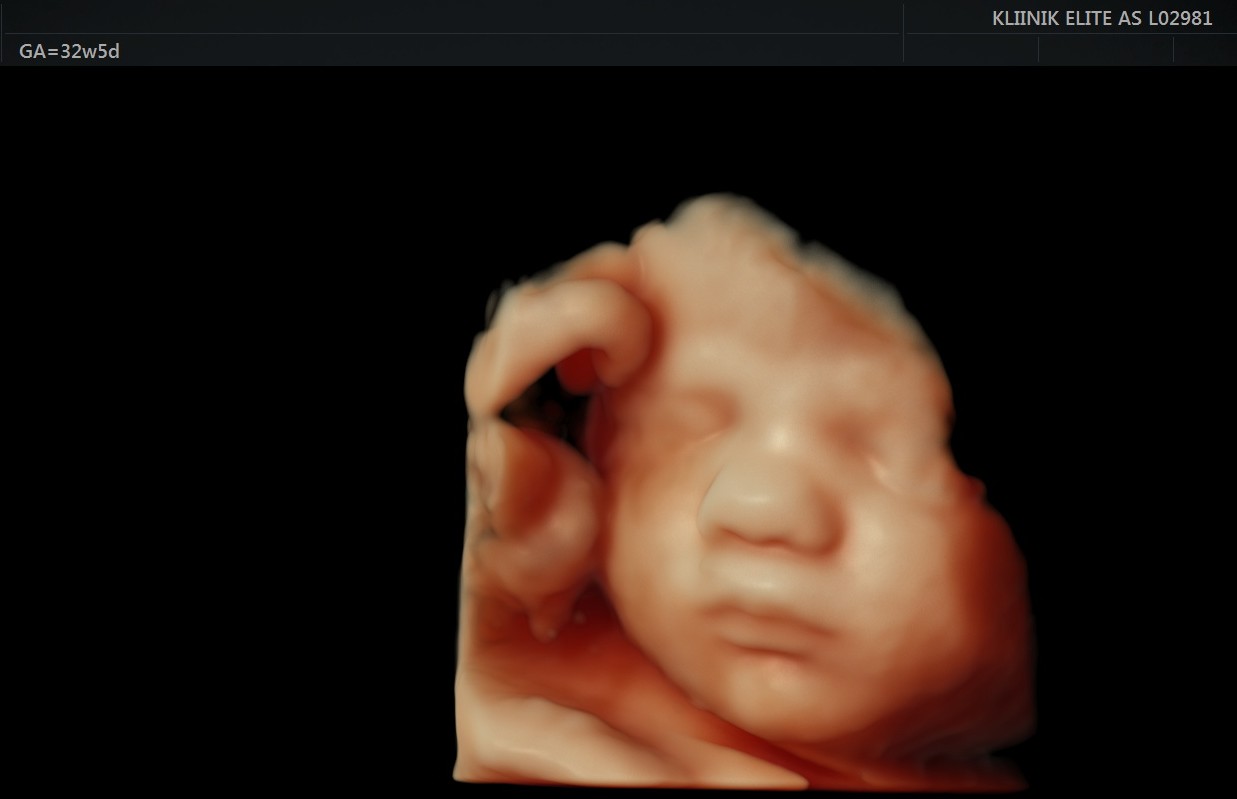

Loote luud hakkavad tugevnema. Kopsudes moodustub aine, mis hingama hakkamisel aitab kopsudel avaneda. Loode teeb regulaarseid hingamisliigutusi. Loote nahk muutub vähem läbipaistvaks. Loote silmad reageerivad valgusele. Loote nahk on kortsuline ja tumepunane. Loote lõug muutub ümaramaks ning jalalaba suurus on umbes 2 sentimeetrit.

Loote kaal on umbes 1 kilogramm ja ta on 35 sentimeetri pikkune. See on parim aeg 4D ultraheliuuringu käigus loote näo vaatamiseks.

See on aeg, mil võiks hakata tasapisi mõtlema sünnituse peale ja uurida, keda sooviks naine sünnitusele tugiisikuks. Sel ajal on võimalik koos käia ka 4D ultraheliuuringul, mis annab infot lapse tervise ja arengu kohta ning võimaldab tulevastel lapsevanematel jälgida reaalajas oma lapse tegevust, tekitades elevust ja pakkudes positiivseid emotsioone.

- Soovi korral 4D ultraheliuuring